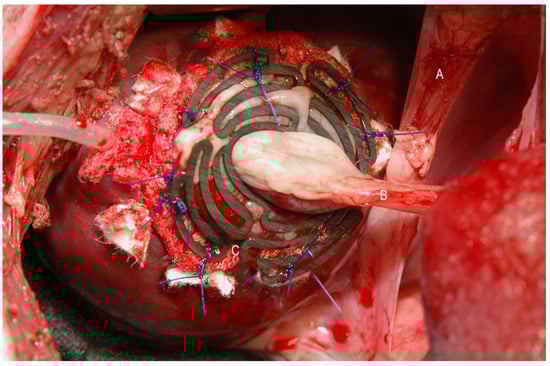

Figure 3. Operative situs using a degradable magnesium scaffold (C) to stabilise an autologous vascularised segment of the stomach (B), which served as a myocardial prosthesis. The gastric section was mobilized into the thoracic cavern via the diaphragm (A).

After manufacturing the degradable magnesium scaffolds (Figure 1 and Figure 2), a left ventricular transmural defect in six Lewe minipigs was covered with a vascularised segment of the autologous stomach (Figure 1 and Figure 3). The native vascular supply of the stomach via the left epigastric vein and artery was maintained. To stabilise this biological graft, magnesium structures were fixed to the epicardium over the reconstructed area (Figure 1, Figure 2 and Figure 3).

First, a transmural and nearly circular defect measuring approximately 4 × 4 cm was produced in the anterolateral wall of the left ventricle. The diaphragm was incised, and the prepared segment of the stomach, including its native vascular supply via the left epigastric artery, was positioned through this incision into the thoracic cavity. The stomach was then closed with a continuous suture (Polyprolene 2.0, Ethicon, Hamburg, Germany). The stomach segment was mechanically freed from its mucosa with a scalpel and drawn through the central ellipsoid opening of the magnesium scaffold. The circular transmural defect of the left ventricle was then covered with the stomach segment. The vascularised stomach segment was fixed with a continuous suture (Polypronlene 4.0, Ethicon, Hamburg, Germany) to the myocardium. To stabilise the stomach segment against the high intraventricular pressure, the magnesium scaffold—still hanging loosely around the pedicle—was pushed forward until it rested with its outer edges on the epicardium and finally sutured with 4 simple interrupted stitches (Polyprolene 4.0, Ethicon, Hamburg, Germany) to the epicardium, each approximately 5 mm beyond the border zone between the stomach and myocardium (Figure 3).